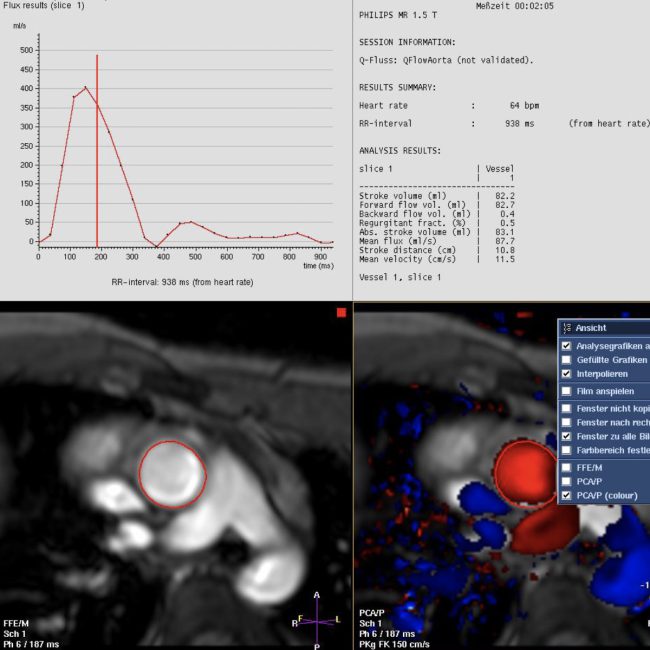

Mit einer Auswertesoftware können sämtliche quantitative Flussparameter erstellt werden. Dazu zählen die durchschnittliche und maximale Flussgeschwindigket, die Flüssigkeitsmenge pro Schlag sowie die Vor-und Rückwärtsflussmengen.